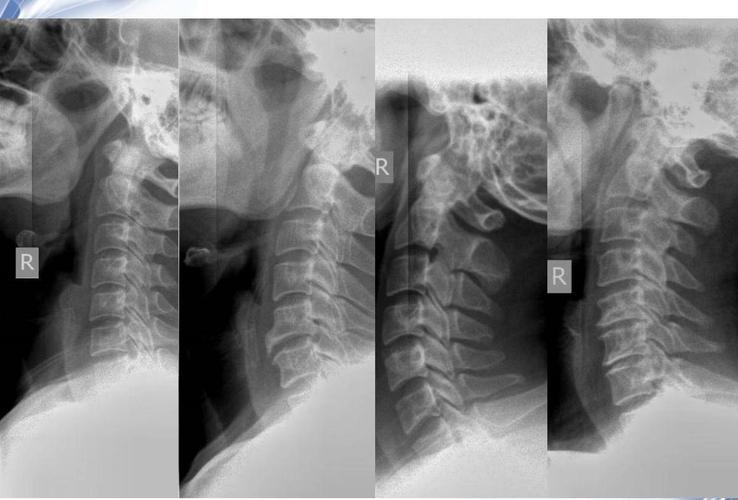

颈椎X光后多久可以怀孕

医院里的检查项目有很多,而平常难免会有磕碰的时候,对于有可能涉及到,比如说颈椎X光多久可以备孕,这个很多人都不清楚。那么到底颈椎X光后多久可以怀孕呢?颈椎X光多久可以怀孕呢?